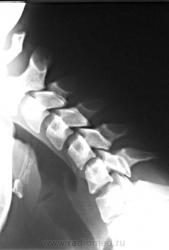

Дело в том, что именнов этом ПДС, определяется фиксация и ограничение объёма движений. Как видите - ни при згибании, ни при разгибании ширина и форма межпозвонкового диска не изменяется. Да и форма тела С5 мне кажется весьма отличной от других тел... Такое впечвтление, что сформирован неоартроз.

Там действительно есть неоартроз с деф артрозом, но  это точно не сами позвонки, а части избыточно развитых отростков...

Спасибо Анатолий Иванович, понял что это гиперплазированные поперечные отростки тел С5 и С6, с сформированым между ними неартрозом и деф. артрозом. Вообще эта пациентка какаято странная - жалуется на похудение одной (правой) половины тела. Напрвляли её на ПКОП - ничего кроме сколиоза, с небольшим торсионным компонентом нет. Тут вот шейный отдел, надо бы грудной снять, а тут опять кто то из врачей сказал, что много уже рентгена и на грудной не направили...